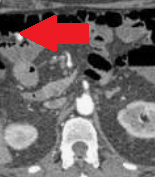

CT κοιλίας. Κόκκινο βέλος — Τυφλίτιδα. Σημαντική πάχυνση τοιχώματος τυφλού (Ευγενική παραχώρηση Dr. V. Penopoulos)